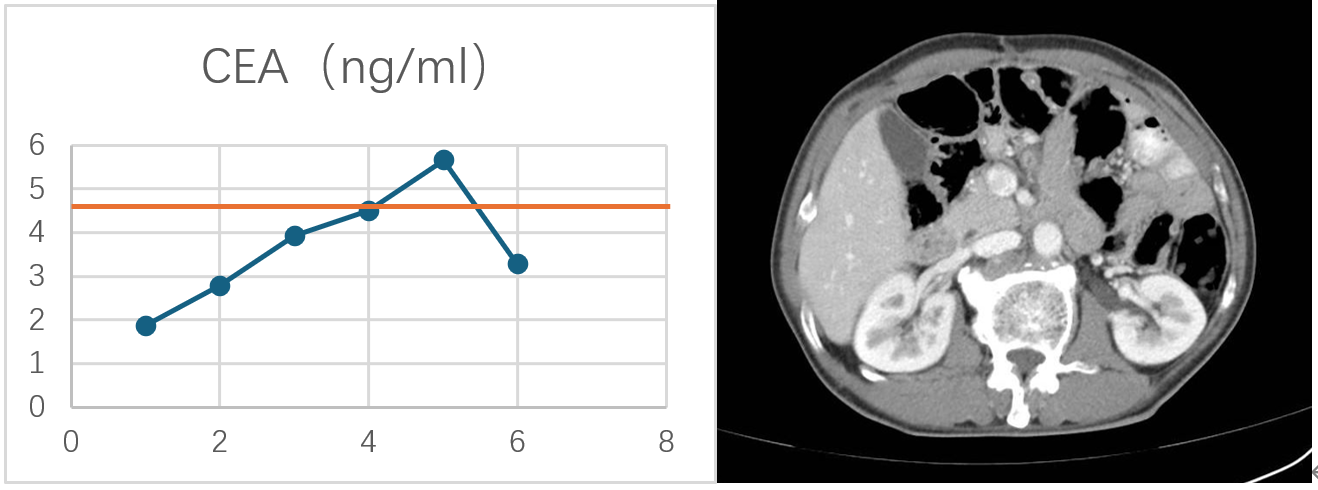

血清CEA变化:经过一个周期的治疗后,血清CEA就降至正常,之后都保持在正常水平。其余肿瘤标志物均未升高,在正常范围内。

CEA变化